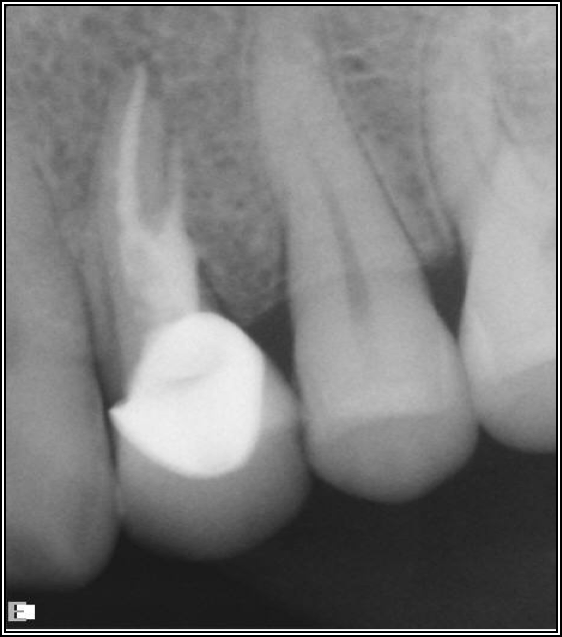

Figure 2 shows a situation where the clinician excavated the tooth of a patient with decay, and it pulped out. The buccal and lingual walls were intact; however, the walls were minimal, and there were still fragments of amalgam and cracks. If the clinician prepared this tooth after building it up, the clinician would lose all the good tooth structure that was left. This tooth would likely need a post.

Fig 2. Minimal walls.

Figure 2